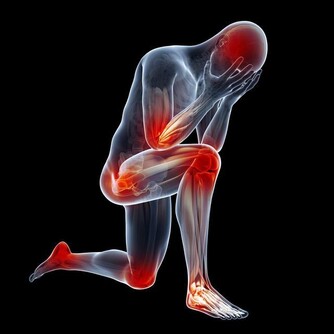

瘙癢其實是秋季常見的疾病,一般來說,吃刺激性食物或升高體溫容易誘發或加劇瘙癢。